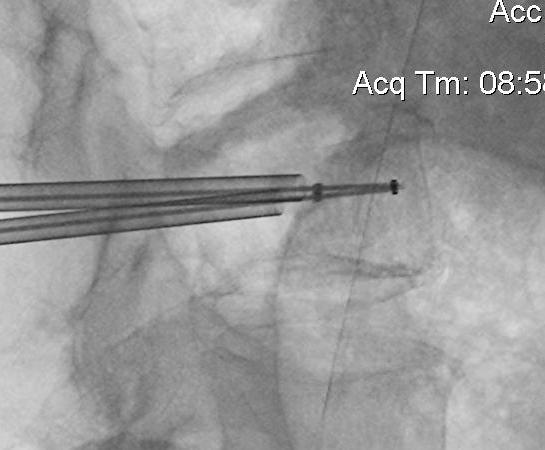

Technique

Insert a balloon first and inflate

- bilaterally into each pedicle

- will restore some anatomy

- then inject PMMA